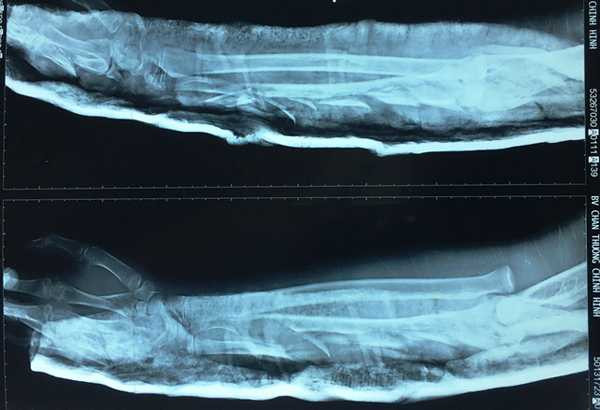

Cánh tay bị chém đứt của cháu bé qua phim chụp X-quang.

Các bác sĩ chẩn đoán bệnh nhân mang vết thương nhiều tầng mặt sau cánh tay và cẳng tay đến cổ tay, đứt nhiều tầng cơ tam đầu, dập đứt nhiều tầng toàn bộ cơ mặt sau cẳng tay, gãy nhiều tầng xương trụ, trật chỏm quay, gãy xương thuyền, xương cả, xương bàn ngón IV, V tay trái.